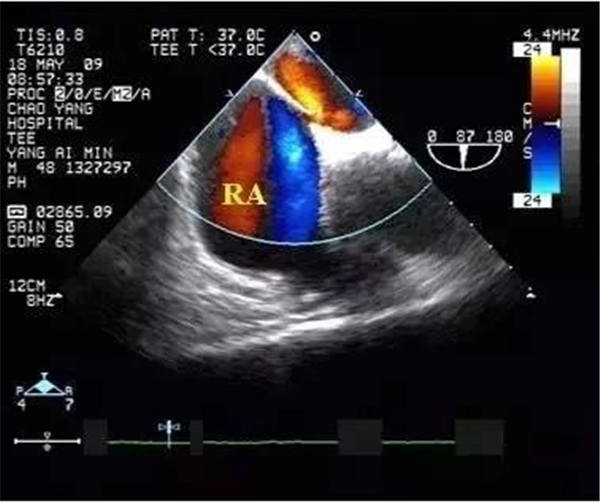

血栓

血栓是血栓性肺栓塞最典型的特征,位于右房或右室中的血栓可形态各异,而位于肺动脉内时则常表现为大块血栓,从主干延续至一侧或双侧肺动脉分支。右肺动脉主干血栓易于显示,左肺动脉因显示较短,血栓不易显示。此外,需注意将血栓与右心系统肿瘤相鉴别。

右心血栓 肺动脉血栓

卵圆孔(PFO)重新开放

慢性血栓性肺栓塞患者,由于肺动脉高压常造成PFO重新开放。往往会造成矛盾性栓塞。

临床上可通过右心声学造影判断卵圆孔开放与否,经食管超声心动图则可显示卵圆孔分流。